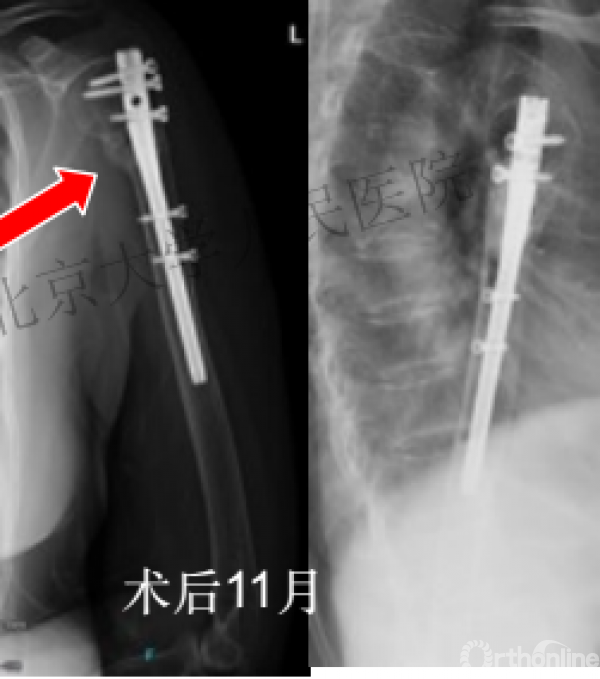

复位良好的标准:颈干角:135°,大结节与肱骨头距离:8mm

术后3月随访:继发性颈干角变小22°(5-82),肱骨头内翻,达46%

严重影响了患者的生活质量